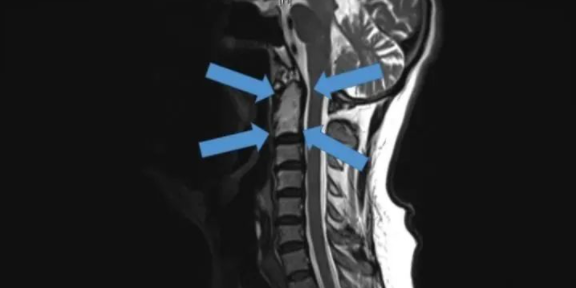

△2015年底,世界首例采用3D打印椎骨植入物

脊柱行业也是未来医疗器械市场,最新发展趋势之一。通过3D打印技术,来达到创新产品的目的,该技术可以促进骨骼向内生长,并改善植入物对脊柱骨的固定,缩短制造流程,提高患者满意度,从而在某些情况下更具成本效益。

例如,Medtronic钛金属3D打印平台——TiONIC技术。使用激光方法制造具有增强表面纹理的植入物。Artic-L是该公司使用TiONIC技术制造的第一款金属植入物。可供外科医生在脊柱手术中使用。还有K2M的Lamellar,同样采用钛制造3D脊柱植入物。使用金属3D打印技术特有的优势之一,可实现曾经被传统制造技术,认为不切实际的结构。

△TsunamiMedical、SeaSpine和Osseus等脊柱公司,采用3D打印制造脊柱